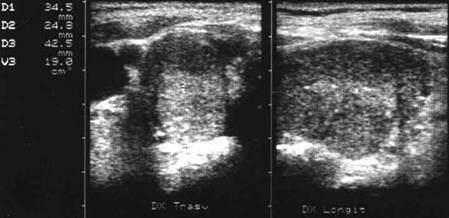

Lob drept , proiectie trasversala si longitudinala.

Femeie 19 ani. Leziune marcant hipoecogen cu intarire posterioara, de 16x20x26mm (4 cc) in lobul drept.

Examen citologic: macrofagi, fara tireocite.

Femeie 17 ani. Voluminoasa tumefactie (32x40x45mm, 29 cc) in lobul stang, intens hipoecogena, cu echo densitati in interior, intarire posterioara. Deviatia tracheei spre dreapta.

Examen citologic; chist coloid